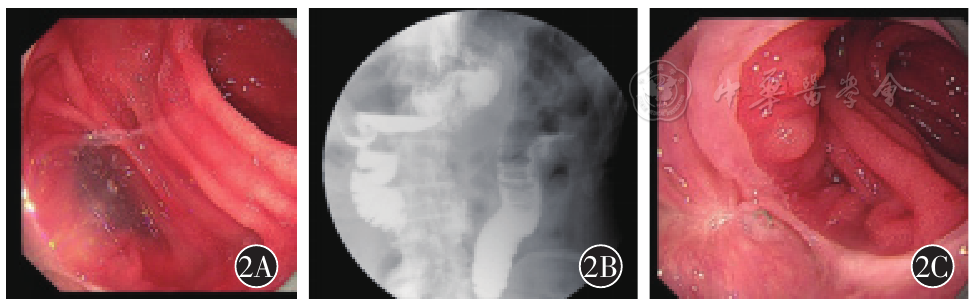

A retrospective analysis was conducted on the clinical data of 11 patients who underwent total laparoscopic proximal gastrectomy with digestive tract reconstruction via λ-shaped uncut jejunojejunostomy from October 2023 to April 2024. Their clinical characteristics, perioperative indicators, postoperative outcomes, and follow-up results were analyzed. Gastroscopy, upper gastrointestinal radiography, and nutritional scoring were combined to evaluate postoperative reflux esophagitis and nutritional status of the patients.

All 11 patients successfully underwent the target surgical anastomosis for digestive tract reconstruction. The perioperative indicators were as follows: mean operation time (192.9±36.2) minutes, intraoperative blood loss (104.5±47.2) ml, time to first postoperative flatus (3.5±0.5) days, time to first oral intake (4.5±0.5) days, length of hospital stay (15.3±1.7) days, and the number of lymph nodes dissected was 44. The mean prognostic nutritional index (PNI) was (54.7±6.1) preoperatively, (45.2±6.3) at 1 month postoperatively, (49.7±3.5) at 6 months postoperatively, and (52.8±4.2) at 12 months postoperatively. No early complications occurred in the 11 patients. The total incidence of late complications was 27.2% (3/11): 1 case of esophageal anastomotic stricture, which improved after endoscopic dilation therapy; 1 case of reflux esophagitis (LA-B grade) and 1 case of gastroesophageal reflux symptoms, both of which were relieved after dietary education and drug treatment.